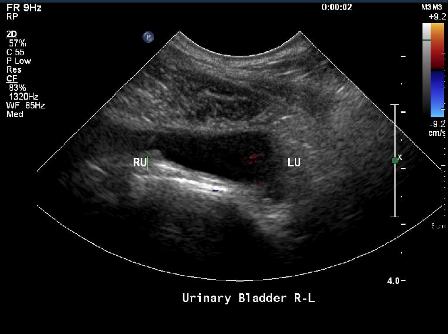

Ultrasound of Dog Bladder Suffering from Urinary Incontinence

Exam also based on use of endoscope. Together confirmed case of Canine Urethral sphincter mechanism incompetence

Source: Sean Stockwell Cornell University School of Veterinary Medicine